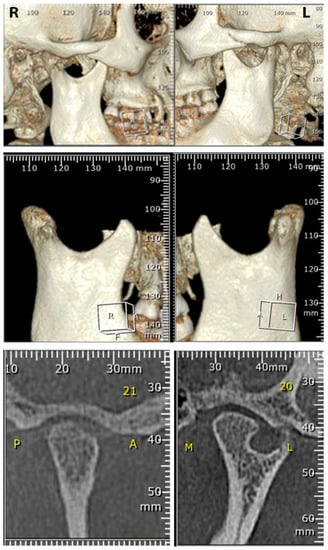

Figure 3.

Images showing the tomographic view of the condyles sitting on the mandibular fossae, as well as the heart-shaped mandibular condyle on the left TMJ (bottom), which is a consequence of the condylar fracture. R: Right; L: Left; P: Posterior; A: Anterior: M: Medial; L: Lateral.

After ten years of completing the myofunctional treatment, new records, including photographs, as well as a TMJ tomogram, were taken. The clinical exam revealed the patient’s facial appearance, and craniofacial growth and development has continued within normal limits, maintaining a symmetric growth at the craniofacial complex (Figure 1). The dental occlusion stays symmetrical on both sides, with a normal vertical dimension, as it was at the end of the treatment ten years before (Figure 2A). The opening of the mouth (Figure 2B), as well as the mandibular lateral excursions, are currently under normal limits, demonstrating that the mandibular dynamics are within a normal range of motion (Figure 2C,D). The most recent tomogram revealed that the mandibular condyles are sitting in the mandibular fossae (Figure 3—upper), the right mandibular condyle has a normal shape, and the left mandibular condyle has a heart-shaped morphology, as was observed at the end of the myofunctional treatment and previously reported (Figure 3 middle and bottom). Besides that, the patient has not felt any symptoms, nor does the patient present any signs of temporomandibular dysfunction or craniofacial pain.